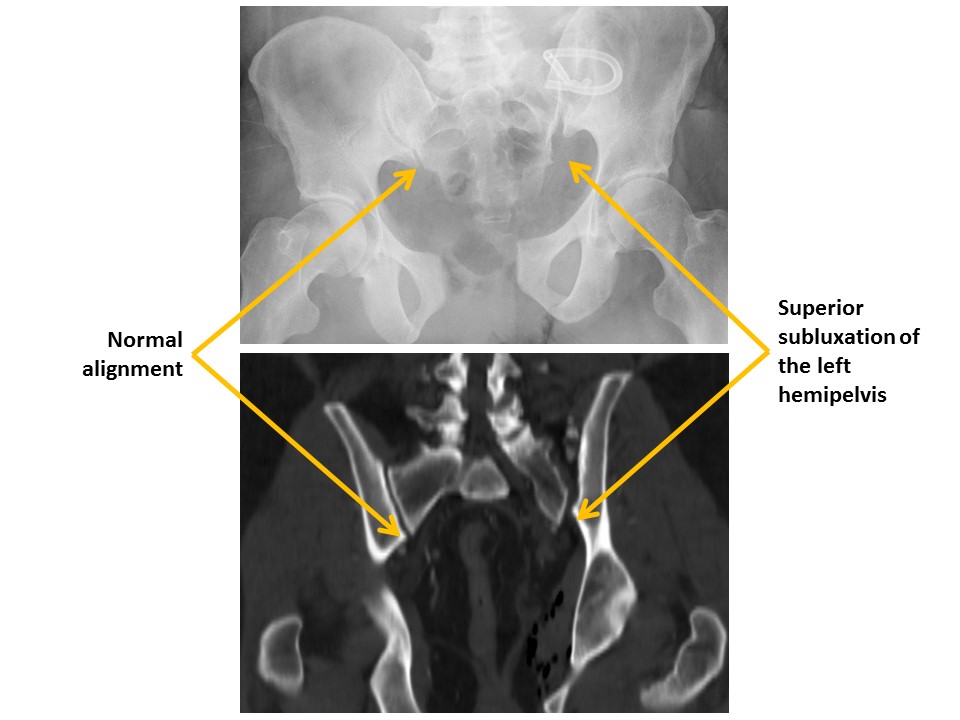

The sacroiliac joints are widened and asymmetric. [Yes/No]

There is malalignment at the inferior margin of the sacroiliac joints. [Yes/No]

The pubic symphysis is widened or vertically incongruent. [Yes/No]

Ilioischial lines are disrupted. [Yes/No]

Iliopubic (iliopectineal) lines are disrupted. [Yes/No]